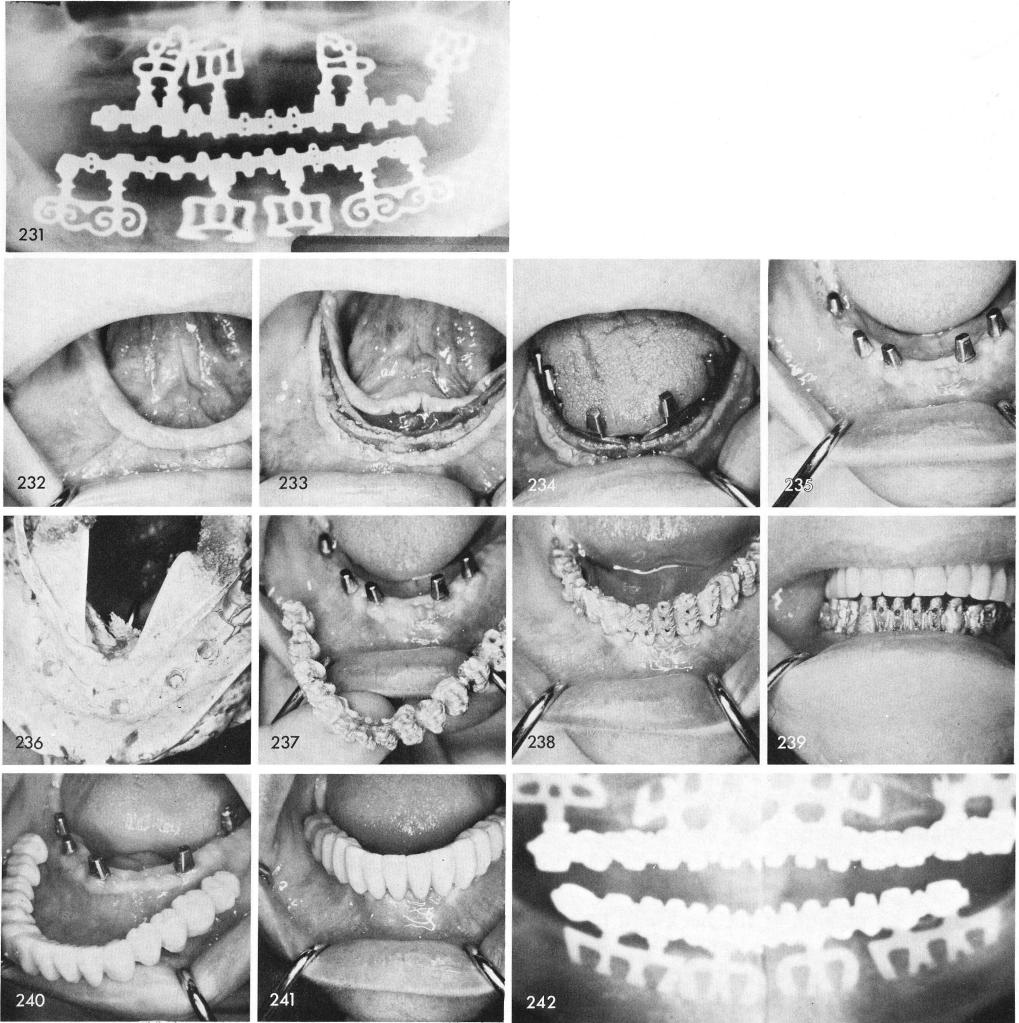

One must be careful when reflecting the tissues of a patient whose mandible contains a "labial roll over", fig. 232. Very often if not careful the tissues that are reflected beneath the labial bulge can be torn, thus slowing down the healing mechanism. In this case, however, a clear reflection was possible, fig. 233. Blades were symmetrically inserted, fig. 234. Healing was uneventful, fig. 235. An elastic impression of the posts was taken, fig. 236, for the casting of a one piece superstructure, figs. 237, 238, 239 and to accommodate the processing of acrylic teeth, figs. 240, 241. This x-ray was taken seven years post-operatively, fig. 242.